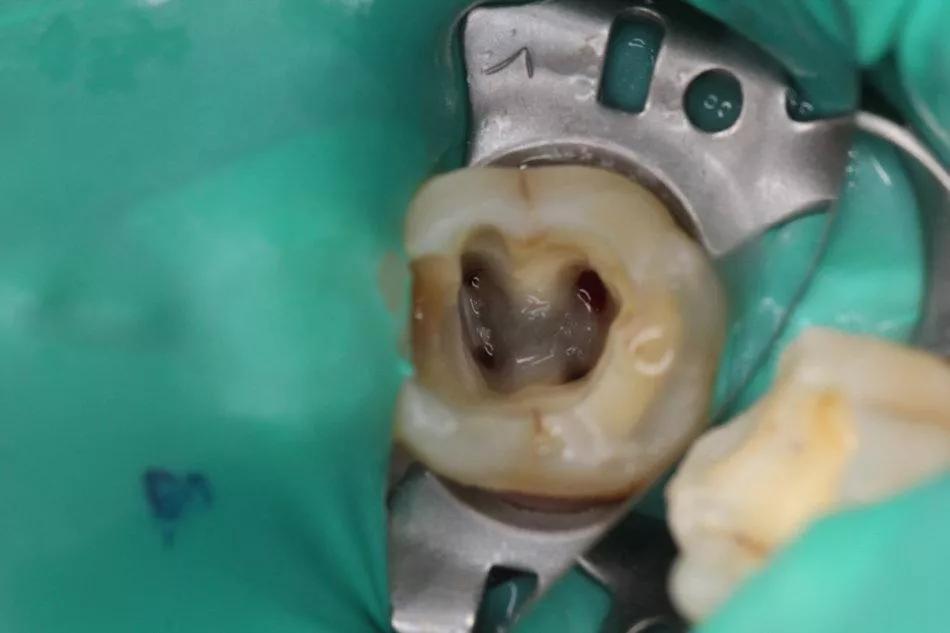

3.绿色橡障如图2,做根管时照在嘴上,减少了张嘴的疲劳,像手术洞布,只漏出坏牙